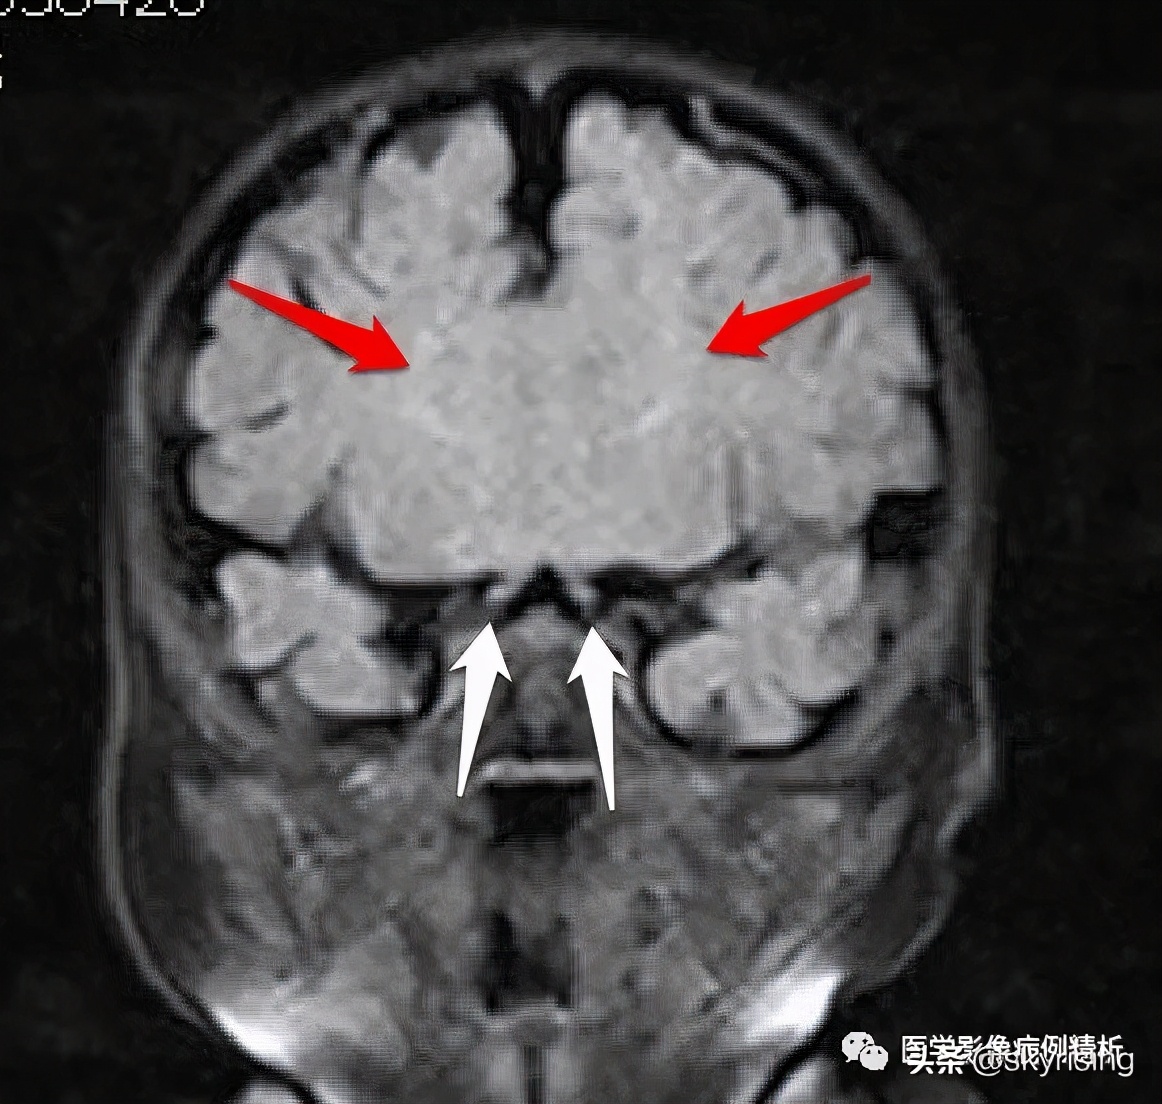

T1WI矢状位:红色箭头所示胼胝体嘴部、膝部、体前部缺如,正常扣带沟形态消失,双侧额叶延伸至侧脑室内。

红色箭头所示为融合额叶脑实质,大脑纵裂不完全。白色箭头所示为双侧视神经,形态对称、大小、信号未见异常,提示视神经发育正常。

T1WI冠状位如下图所示,红色箭头为扣带回外翻,未能形成扣带沟;白色箭头可见Probst束,沿侧脑室壁向下走行。